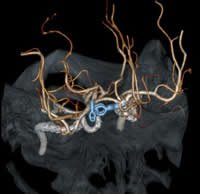

検査は、ベッドに寝ているだけで終了します。また、当院検査は、一回の撮影で同時に複数の輪切り像が得られる最新型ボリュームCTスキャナです。 得られた輪切り画像から下のような精密な立体像を作ることも可能です。

脳血管3次元画像